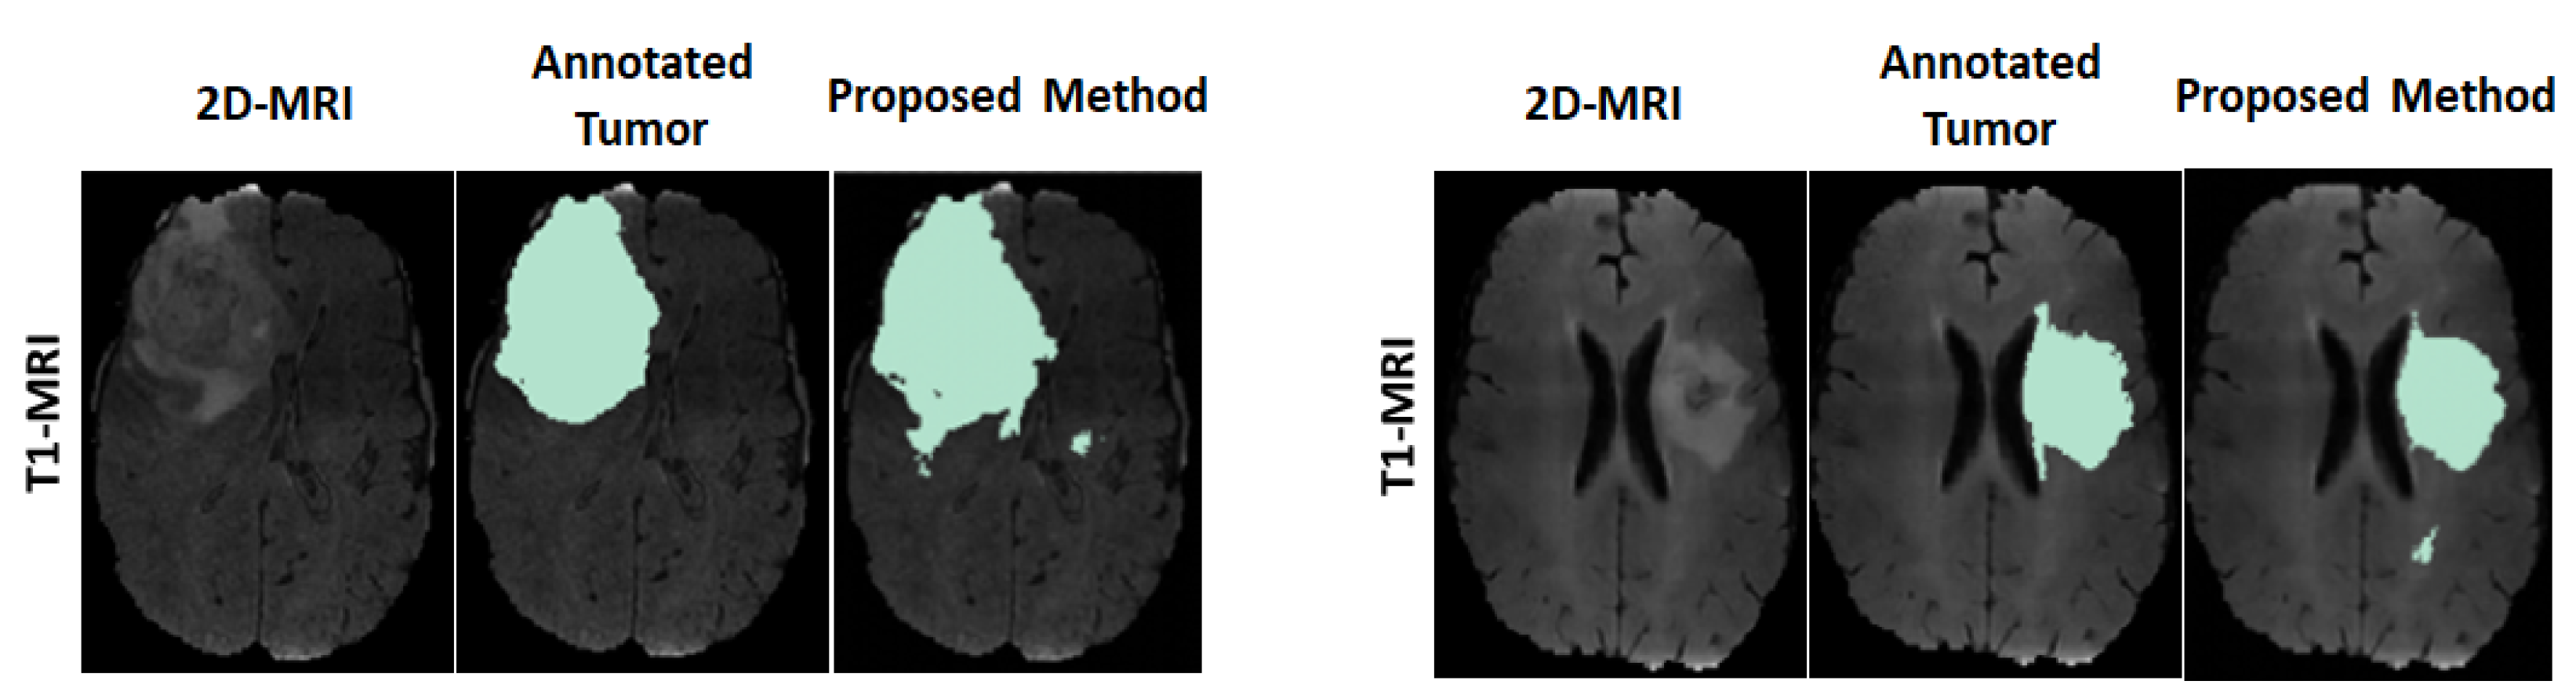

3.2. Results, Comparison and Discussion

3.2.1. Results

3.2.2. Comparison

3.2.3. Discussion